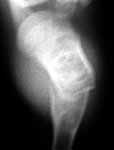

On 6th September 2003, he sustained refracture due to trivial trauma while he was not using the brace and X rays taken this time are also attached. Now that the lesion has migrated to the centre with growth and looks ?less in size compared to 2 years ago, should I advise curettage and bone grafting now? My clinical diagnosis is fibrous dyslasia. In case surgery is advised, do it immediately or wait for the fracture to get sticky.

6-9-03